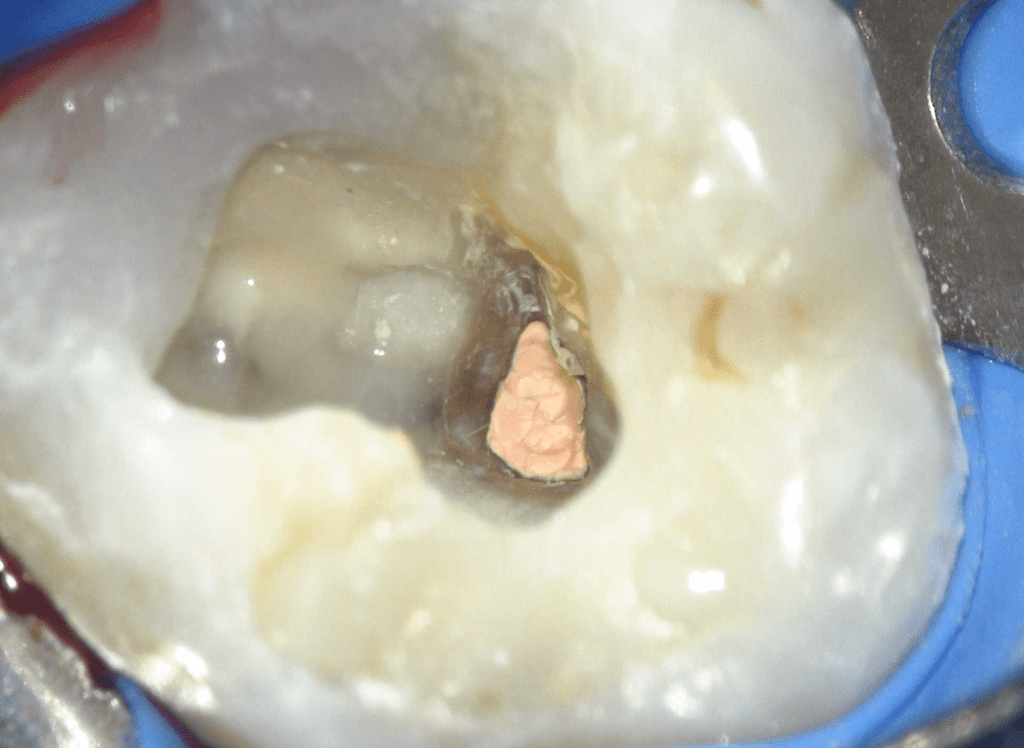

Reconstrucción preendodóntica

Reco pared vesticular

Reco pre-endo, molar inferior